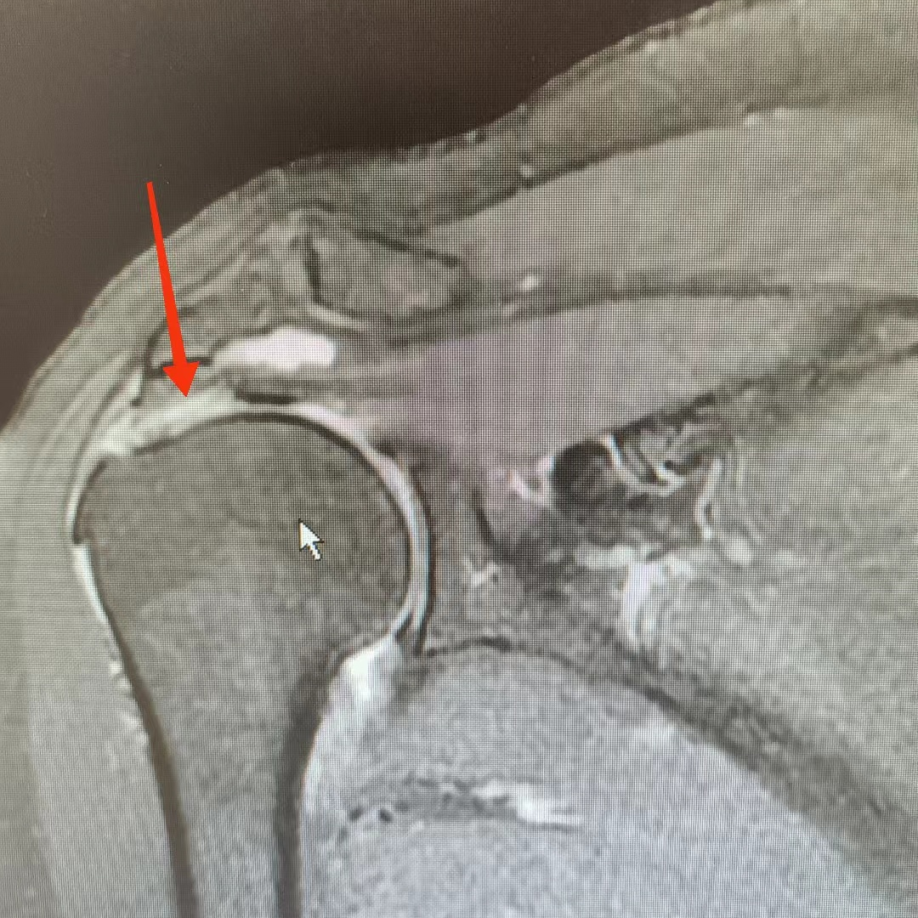

周武忠主任讲到,肩袖损伤的诊断,主要是要靠病史、症状、康复查体还有一些必要的影像学检查。其中MRI可以清楚地显示出肩袖的发病部位以及撕裂的严重情况,可以准确地确定肌腱损伤的位置和严重程度。肩袖撕裂则需要进行手术治疗并在术后进行康复训练以恢复功能。肩袖损伤疼痛的性质可能从迟钝的疼痛到剧烈的疼痛,疼痛会沿着上臂向下移动,对一些人来说,肩痛可能会把他们从睡梦中痛醒。

本月初我们科室接诊了一位患者,以夜间疼痛为重,肩关节活动范围明显减少,活动受限1年余,一直保守治疗,效果不佳,左肩部及活动受限现象无好转。来到我们科后,诊断为左侧肩袖损伤,合并左侧肩关节冻结肩,这种情况如果继续保守治疗是没什么效果的,而且时间长了,病情会更加严重。

手术团队很快为她安排了左肩关节镜下探查、清理+肩峰成型术+肩袖撕裂修复术,手术效果明显,再通过个性化的康复锻炼,一般均会很快康复。我们每个月都会接诊不少肩袖损伤的患者,60岁以上比较常见,经过肩关节镜微创治疗后,效果都很不错。